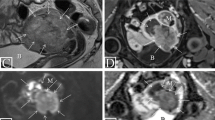

14.2.5 MRI Features of EC

On T2WI, EC appears as a thickened endometrium or a mass, occupying the endometrial cavity. It shows hyperintense SI when compared to hypointense myometrium, and intermediate-low SI relative to hyperintense normal endometrium (Fig. 14.4). Small tumors may not be associated with endometrial thickening or can have a similar SI to that of normal endometrium. In these cases, DWI and DCE are particularly helpful. On DWI, the tumor is hyperintense on high b-value images (800–1000 s/mm2), with a corresponding hypointense SI on the ADC map (Fig. 14.4). On DCE images, the tumor shows an early enhancement compared to normal endometrium and on later phases it appears hypointense relative to the myometrium.

“One-stop shop” approach, FIGO stage II endometrial cancer. A 66-year-old patient with vaginal bleeding. On T2WI there is an intermediate-SI endometrial tumor (a), which interrupts the low-SI of cervical stroma (b, arrow). On DCE (c) the normal enhancement of cervical stroma is disrupted by the hypo-enhancing tumor (arrow) which has restricted diffusion on DWI (d, arrow). The gross examination of the surgery specimen shows the solid tumor (e, arrow). The pathology revealed endometrioid adenocarcinoma involving the cervical stroma (f), consistent with FIGO stage II. These images were originally published in Pintican R, Bura V, Zerunian M, Smith J, Addley H, Freeman S, Caruso D, Laghi A, Sala E, Jimenez-Linan M. MRI of the endometrium—from normal appearances to rare pathology. Br J Radiol. 2021 Sep 1; 94 (1125): 20201347. doi: 10.1259/bjr.20201347. Epub 2021 Jul 8. PMID: 34233457; PMCID: PMC9327760

Stage I: Tumor invasion of < 50% of the myometrial thickness indicates a stage IA tumor, while the invasion of ≥ 50% of the myometrial thickness indicates a stage IB tumor (Fig. 14.5). There are several pitfalls such as tumor extension into cornua, presence of adenomyosis and leiomyomas (Table 14.2) [9, 27, 28]. In such cases, DWI and DCE help better delineate the tumor margins and lead to improved accuracy.

Stage II: Tumor invades the cervical stroma. The hyperintense SI inflammation (edema) within cervical stroma on T2WI may lead to up-staging. The presence of intermediate T2 SI tumor with diffusion restriction and hypo-enhancement on delayed phase DCE suggests cervical stroma invasion (Fig. 14.4) [9, 27, 28].